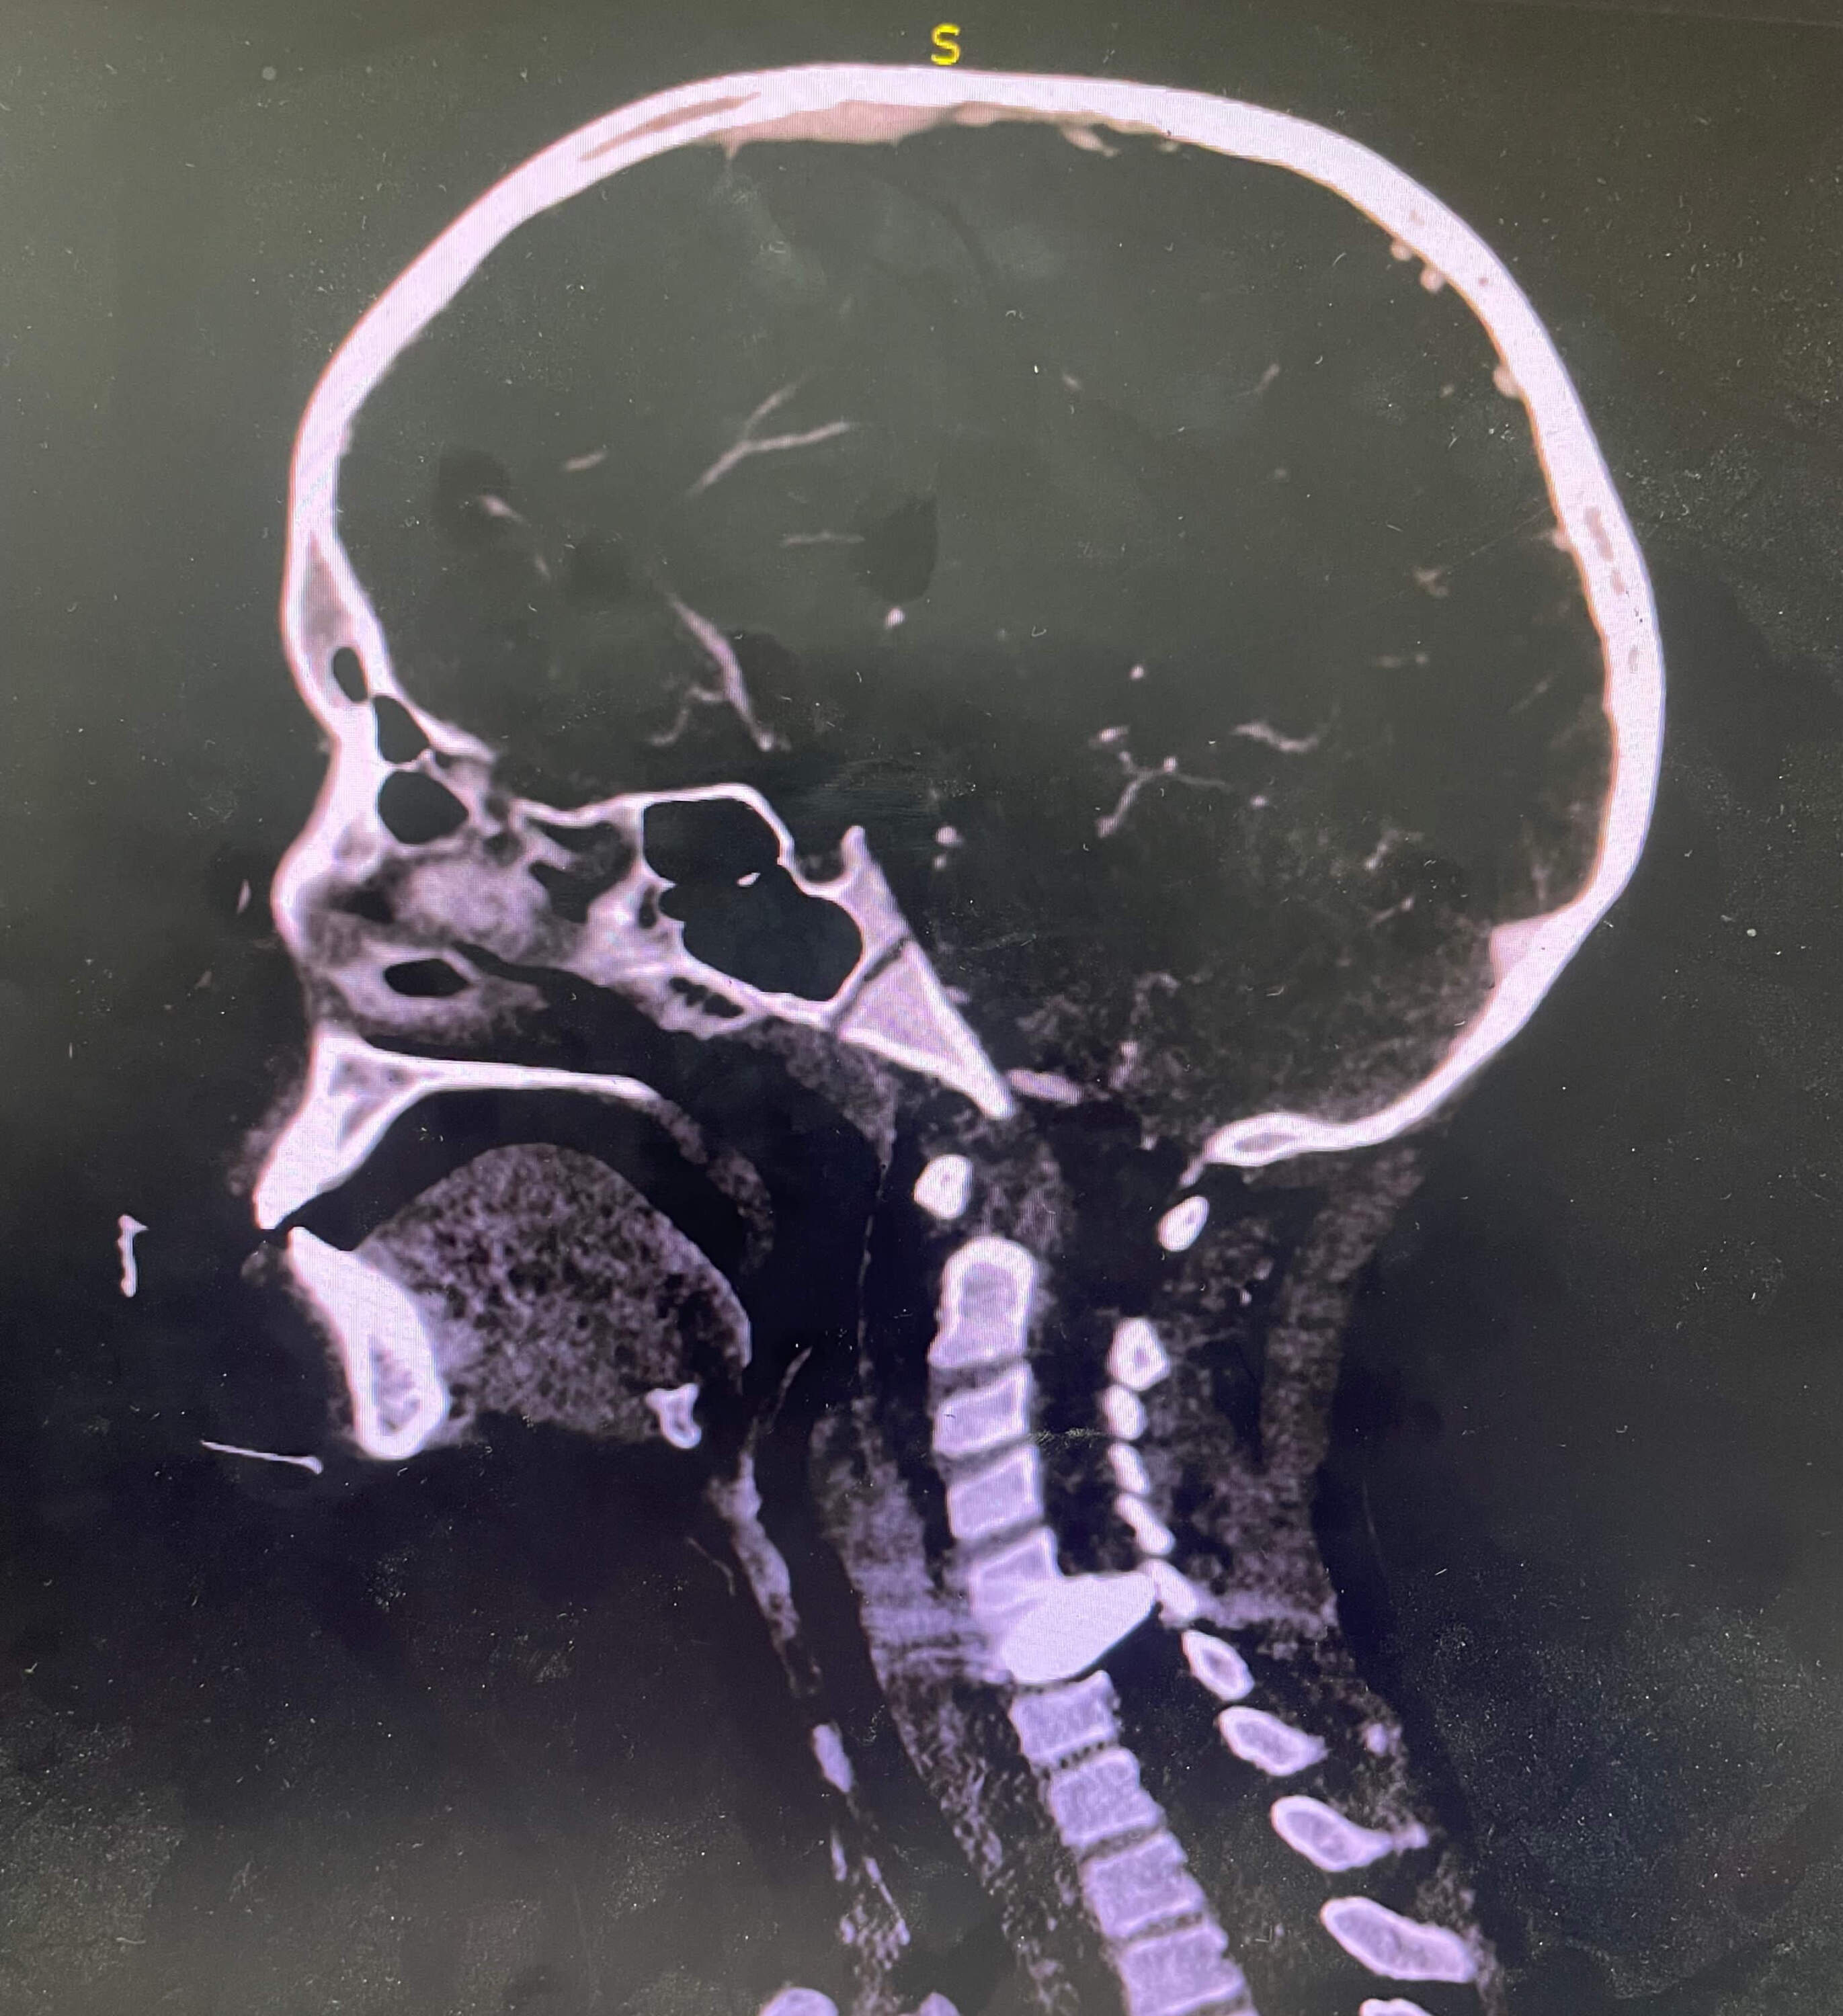

“For example, I just [treated] a young 10-year-old boy, and he had a bag with him that he hoped to fill with food. And he was shot through the face, through the jaw, and it went into his neck — his cervical spine. He's having difficulty moving his arms. He's likely going to be paralyzed.